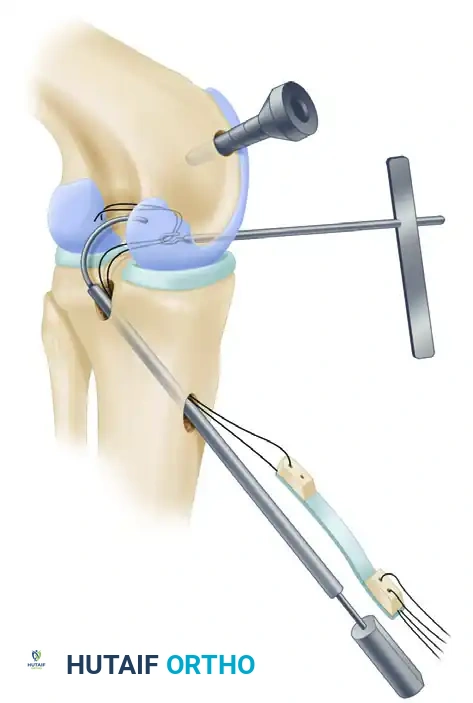

Passing the graft through the acute angle of the posterior tibia (the "killer turn") requires patience and specialized instrumentation.

- Smoothing the Tunnel: Pass a Gore smoother or a specialized rasp through the tibial tunnel, into the joint, and pull it out through the central fat pad portal. Use this instrument to aggressively smooth the posterior aperture of the tibial tunnel and remove any remaining posterior soft-tissue remnants. Do not enlarge the tibial tunnel excessively.

The Arthrex “Worm” Curving Suture Passer facilitates the smooth passing of graft sutures through the tibial tunnel, around the posterior tibia, and into the intercondylar notch.

- Suture Shuttle: Once the smoother passes without undue resistance, attach the graft traction sutures to the end of the smoother or suture passer.

- Pulling the Graft: Pull the graft sutures and the bone plug up through the tibial tunnel and into the joint.

- Troubleshooting: Extreme flexion of the knee sometimes aids the passage of the patellar bone plug from the posterior tibial aperture into the joint.

- Switching Stick Technique: Placing a switching stick through the PM portal allows the guide sutures to be redirected over the stick, acting as a pulley to assist in pulling the graft around the posterior tibial corner.

- Femoral Passage: Place a grasper through the femoral tunnel to retrieve the sutures. Use a probe or an Allis clamp through the AM portal to assist the graft into the femoral tunnel aperture.

- Orientation: Ensure the cancellous portion of the bone plug is oriented posteriorly. This reduces graft abrasion against the sharp anterior rim of the femoral tunnel.